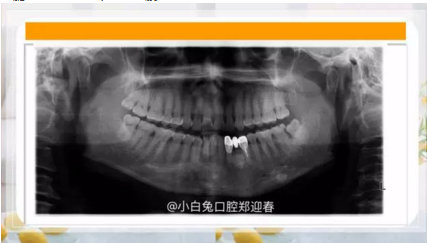

阻生齒外科聯(lián)合正畸治療

25.png

26.png